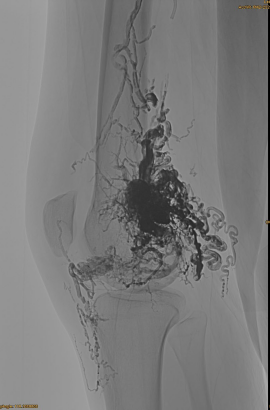

Základní informace pacienta: Žena, 36 let; AVM Pelvis, HIP, Knee, levý OSG, více embolizací pre -.

Počáteční DSA:

Konečný výsledek:

Téměř žádný žilní odliv:

Pozdní fáze, další EMBO je nutná, ale mnohem lepší: